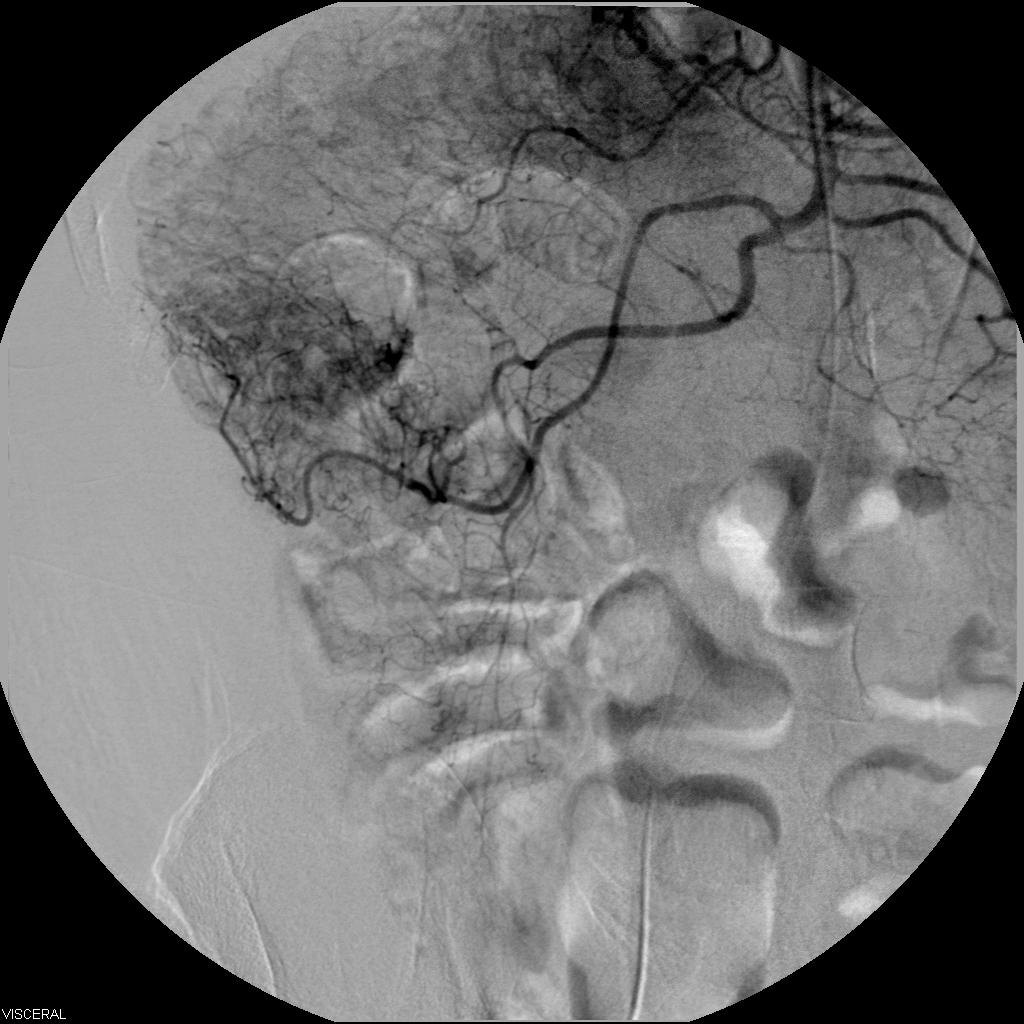

Гемангиома почки: Визуализация ангиографии и диагностические снимки